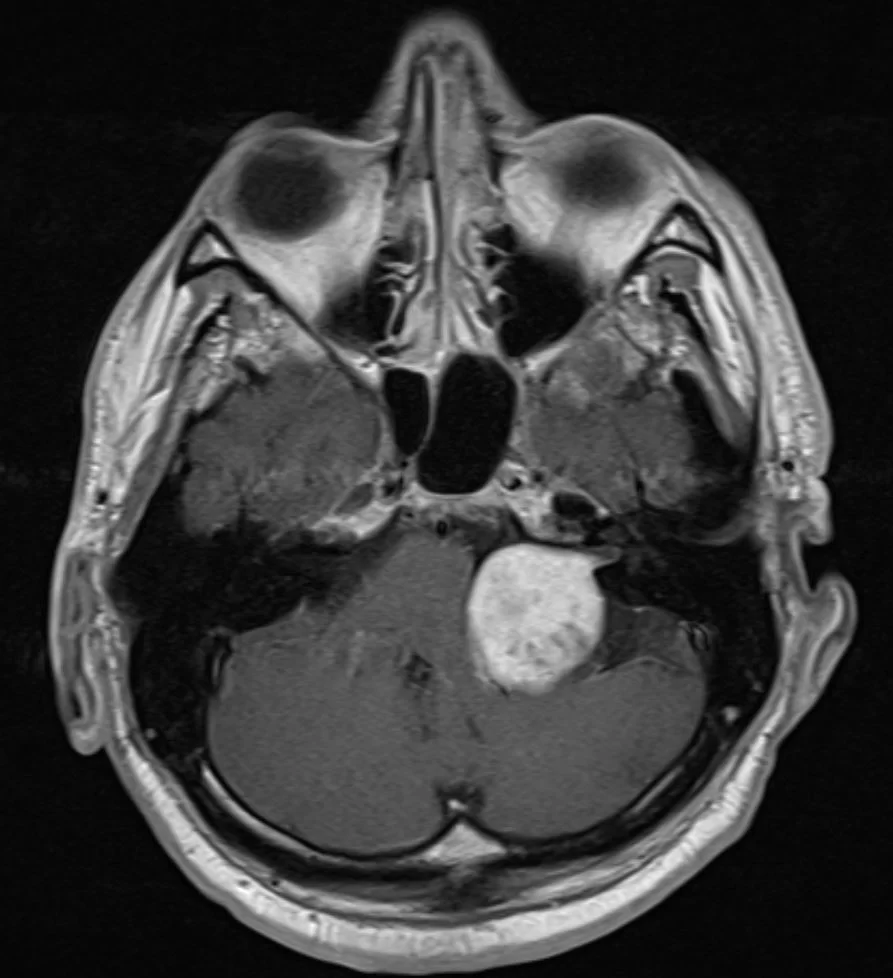

Ευμεγεθες Ακουστικό Νευρίνωμα με πίεση επί του εγκεφαλικού στελέχους

Ασθενής άνδρας, 48 ετών με συμπτώματα εμέτου και αδυναμίας από 15ημέρου περίπου. Στην αντικειμενική εξέταση διαπιστώθηκε σημαντική πάρεση προσωπικού νεύρου αριστερά και αστάθεια βάδισης &